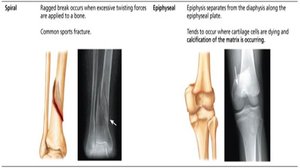

Spiral | Ragged break from excessive twisting; common sports fracture. |

Epiphyseal | Epiphysis separates from diaphysis along epiphyseal plate; occurs where cartilage cells are dying. |